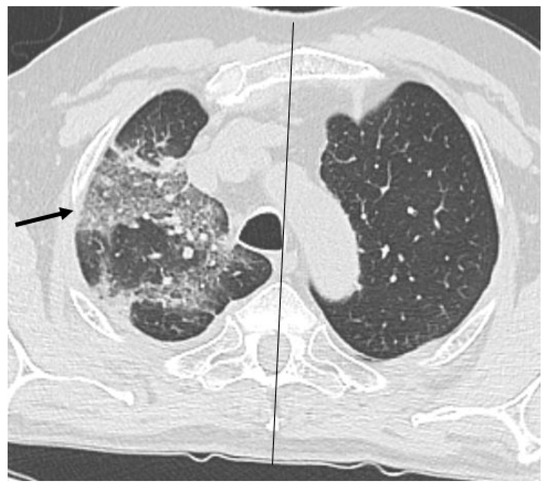

HRCT of the chest showed diffuse bilateral ground glass opacities (GGO) in all patients (Figure 1). Reticulation (Figure 2), traction bronchiectasis/bronchiolectasis (Figure 3), crazy paving and distortion (Figure 4) were observed in 29 patients (64%) at baseline. The total severity score was significantly higher at baseline in patients who eventually developed severe versus non-severe ARDS and pneumomediastinum/pneumothorax (16 versus 14; 95% CI 0.42 to 3.88; p = 0.01), as reported in Table 1. No other significant difference was observed at baseline.

Figure 2.

Reticular pattern (arrows) at baseline and massive pneumomediastinum after non-invasive ventilation in a 60-year-old man.